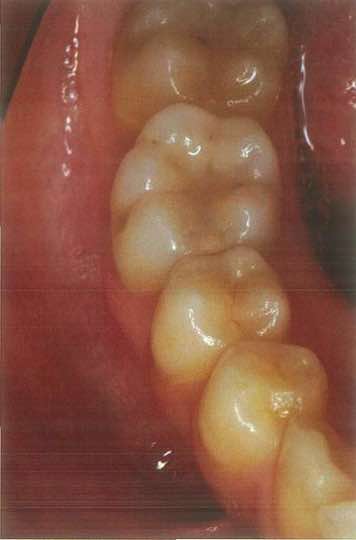

6歳の男児。定期診査を希望して来院した。来院時のエックス線写真を別に示す。

a Hellmanの歯齢はⅢA期である。

b 下顎切歯が1歯不足している。

c 犬歯の歯冠の位置は正常である。

d 下顎第二小臼歯が1歯不足している。

e 第一大臼歯の歯根形成は遅延している 。

正答 b,c

x線の所見は本当に見慣れていないときついです。「c 犬歯の歯冠の位置は正常である。」って自身持って選べる学生は少ないと思います。臨床でがっつり症例こなしたりすると自然に身につくようなもんでしょうけど、学生で教科書にのっている数枚のレントゲンしか見ていない状態だときついものがあります。